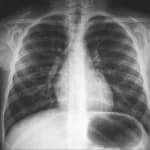

X-ray imaging works by passing a controlled beam of ionizing radiation through the body. Dense structures like bones absorb more radiation and appear white on the image, while softer tissues like muscles and organs allow more radiation to pass through and appear in shades of grey. Air-filled structures such as the lungs appear black. This contrast is what makes X-ray particularly effective for evaluating bones, the chest, and certain abdominal conditions.

Different X-ray views provide different diagnostic information. For example, a chest X-ray is typically taken from two angles, posteroanterior (PA) and lateral, to give a comprehensive view of the lungs, heart, and mediastinum. Bone X-rays may require multiple views to fully assess a fracture or joint abnormality. Your radiologist will determine the appropriate views based on your clinical indication.

Pneumonia & Lung Infections

Chest X-ray can reveal areas of consolidation in the lungs that indicate bacterial or viral pneumonia, as well as tuberculosis and other pulmonary infections.

Heart Enlargement

Chest X-ray can reveal an enlarged heart silhouette (cardiomegaly), which may indicate heart failure, valve disease, or other cardiac conditions requiring further evaluation with echocardiography.

Pleural Effusion

Fluid accumulation around the lungs is visible on chest X-ray as blunting of the costophrenic angles, helping guide further investigation and treatment.